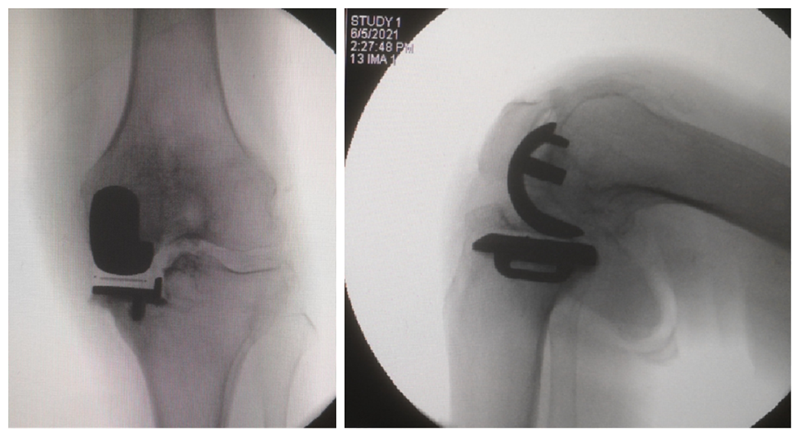

经典内侧单髁置换术(骨水泥型)

术前

术后检查

牛津单髁置换手术最经典的适应证是前内侧膝骨关节炎(AMOA),并且其他结构在功能上应保持完整,尤其强调韧带功能正常。在准备胫骨平台时,应保持7°后倾,截骨位置选在硬化骨下方,磨损最低点下方2mm处,近端紧贴,远端距皮缘18-20mm。试模间隙理想厚度6-7mm(包括胫骨假体3mm+垫片厚度3-4mm)。

在准备股骨侧时,理想状态为试模厚度刚好替换截骨厚度(约3mm),有5个关键点:(1)要保持韧带张力正常,避免过度松弛或过紧。(2)股骨假体位置保持良好,特别注意后髁截骨保持水平,去除骨赘,避免误判屈曲间隙。(3)股骨远端碾磨应保证内侧副韧带在屈膝110°和20°达到张力平衡。(4)要特别注意防撞击,保护内侧副韧带。(5)应采用2步法清除骨水泥。